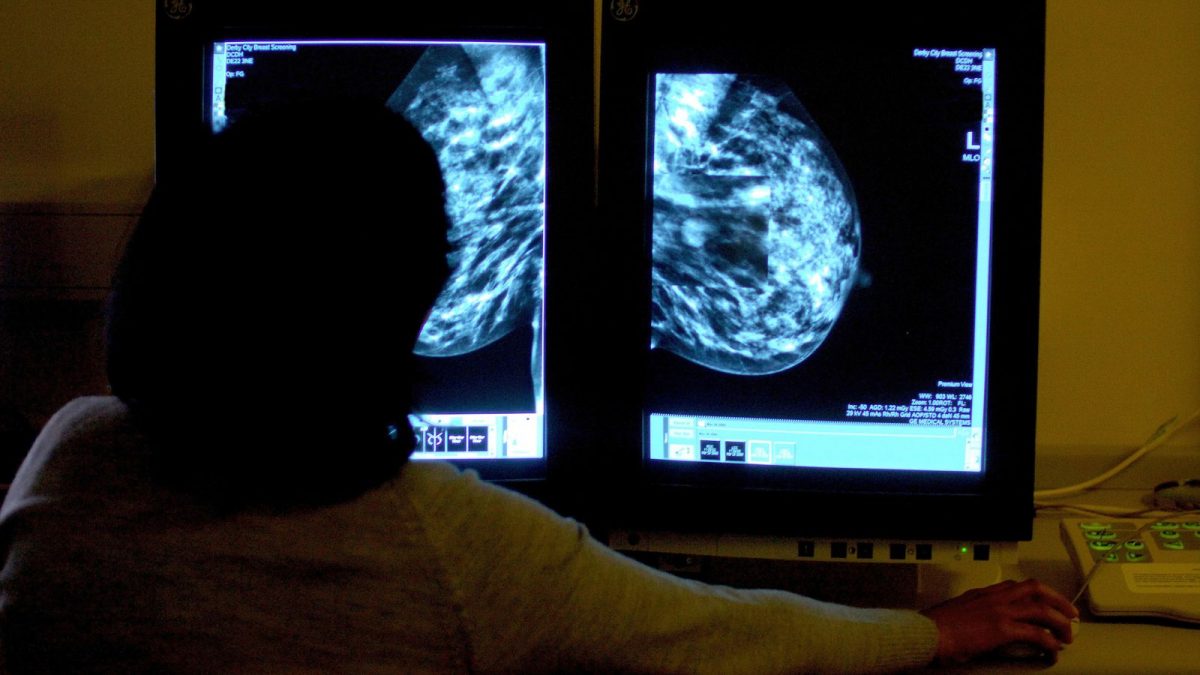

阿斯利康公司的实验性乳腺癌抑制剂camizestrant,可将肿瘤进展或死亡风险降低56%。(图:PA)